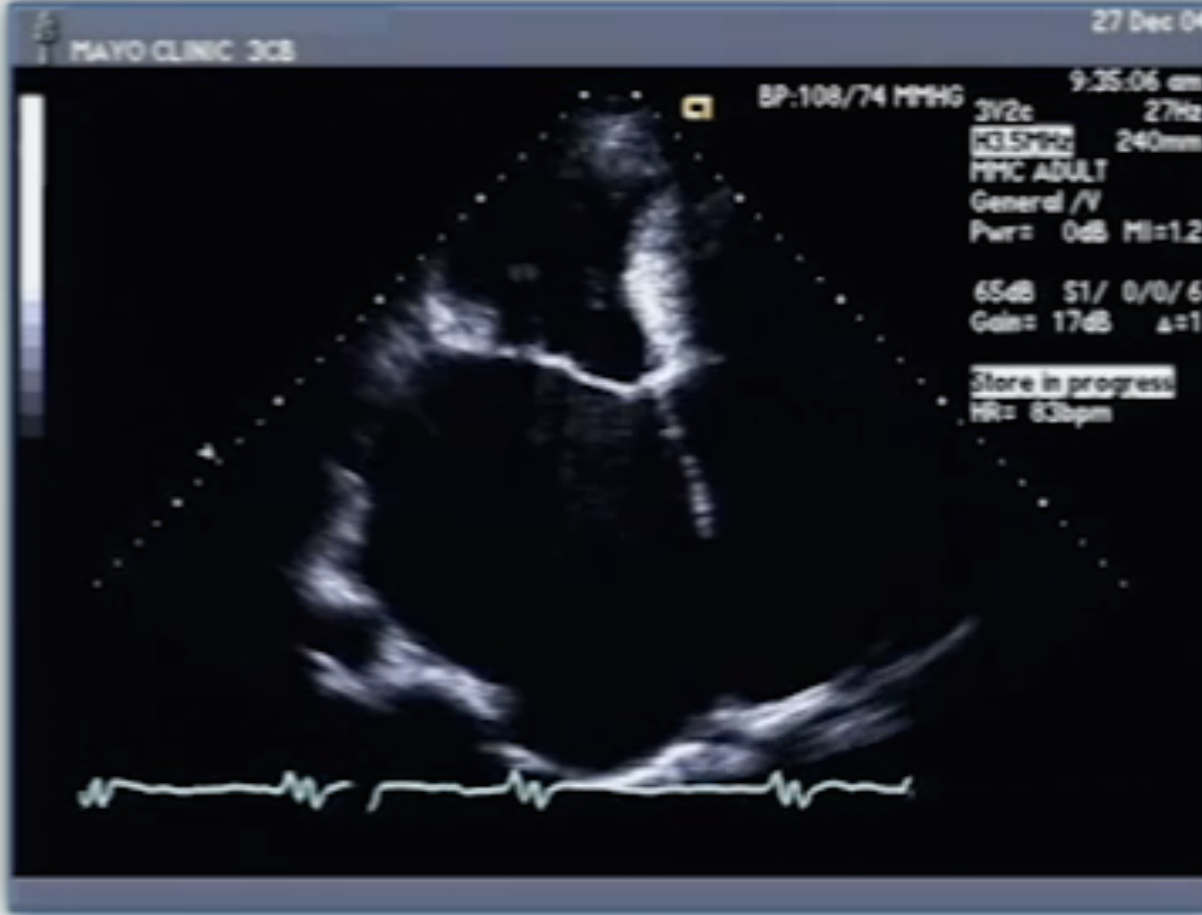

Diagnosis?

restrictive CM